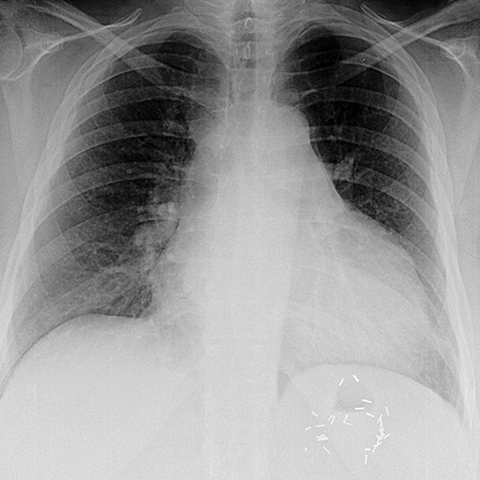

Cardiothoracic Ratio in Cardiomegaly [2 of 2]